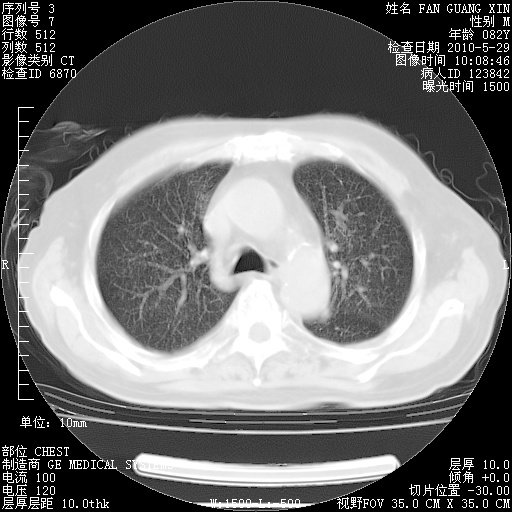

再治疗10天后的肺部CT

再治疗10天后的肺部CT 纵膈窗

从白细胞总数和中性比例看好像合并感染。肺部纹理好像比上次多,支气管炎?其他感染?

阅读此次胸部CT,肺间质渗出性改变较入院时有吸收。目前从体温、白细胞、中性分叶明显增高,肯定存在细菌感染(发生医院感染哦,若无消化道及泌尿系统等感染的依据,肺部感染可能大)。若你院头孢哌酮舒巴坦钠耐药率较高,同意你的方案,若48小时体温仍高,可考虑使用碳青霉稀类抗菌药物,同时可予超声雾化、注意滴数时加大液体量。白蛋白33.30g/L较低哦,需加强营养等支持治疗。